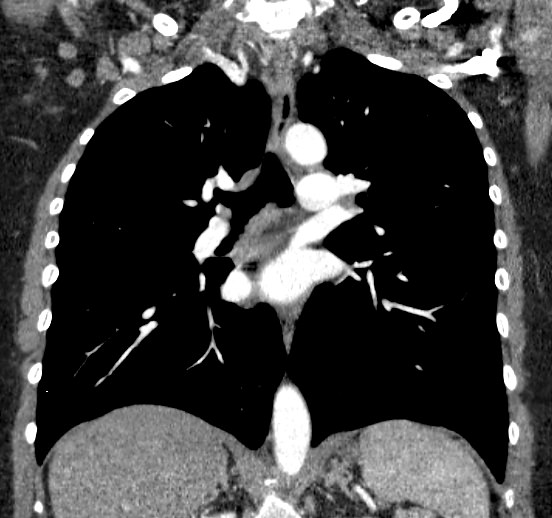

Мультиспиральная компьютерная томография – это современный высокоинформативный рентгенологический метод диагностики различной патологии легких. КТ основана на применении рентгеновского излучения. Однако в отличие от обычного рентгена, при котором снимки делаются в одной плоскости и изображения органов могут накладываться друг на друга, КТ лишена этих недостатков, так как во время компьютерной томографии сканирование проводится в различных плоскостях.

Во время исследования рентгеновская трубка томографа вращается вокруг исследуемой области и производит множество послойных снимков с шагом 0,5-1 мм. Полученные снимки поперечного сечения с помощью компьютерной программы могут быть преобразованы в 3D-изображения исследуемого органа или участка ткани. Это позволяет выявлять практически все заболевания легких на ранних стадиях и назначать своевременное лечение.

В некоторых случаях, например, при подозрении на опухолевый процесс, проводится КТ легких с контрастированием, когда для лучшей визуализации патологического очага пациенту внутривенно вводится йодсодержащий контрастный препарат. Контрастное вещество накапливается в патологических участках и обеспечивает их яркую визуализацию на фоне неизмененной ткани. С помощью контрастирования можно визуализировать кровеносные сосуды, выявить первичные опухоли и метастазы в легких, дифференцировать новообразования, например, отличить доброкачественную опухоль от злокачественной.

В медицинском центре «Доступная медицина» установлено современное оборудование – 64-срезовый и 128-срезовый компьютерные томографы TOSHIBA AQUILION, на которых проводится сканирование легочной ткани. За счет увеличенного количества детекторов аппараты производят снимки с большой скоростью и минимальной дозой облучения. При этом инновационные цифровые приложения позволяют получить объемные изображения легочной ткани высокой четкости, контрастности и в мельчайших подробностях.